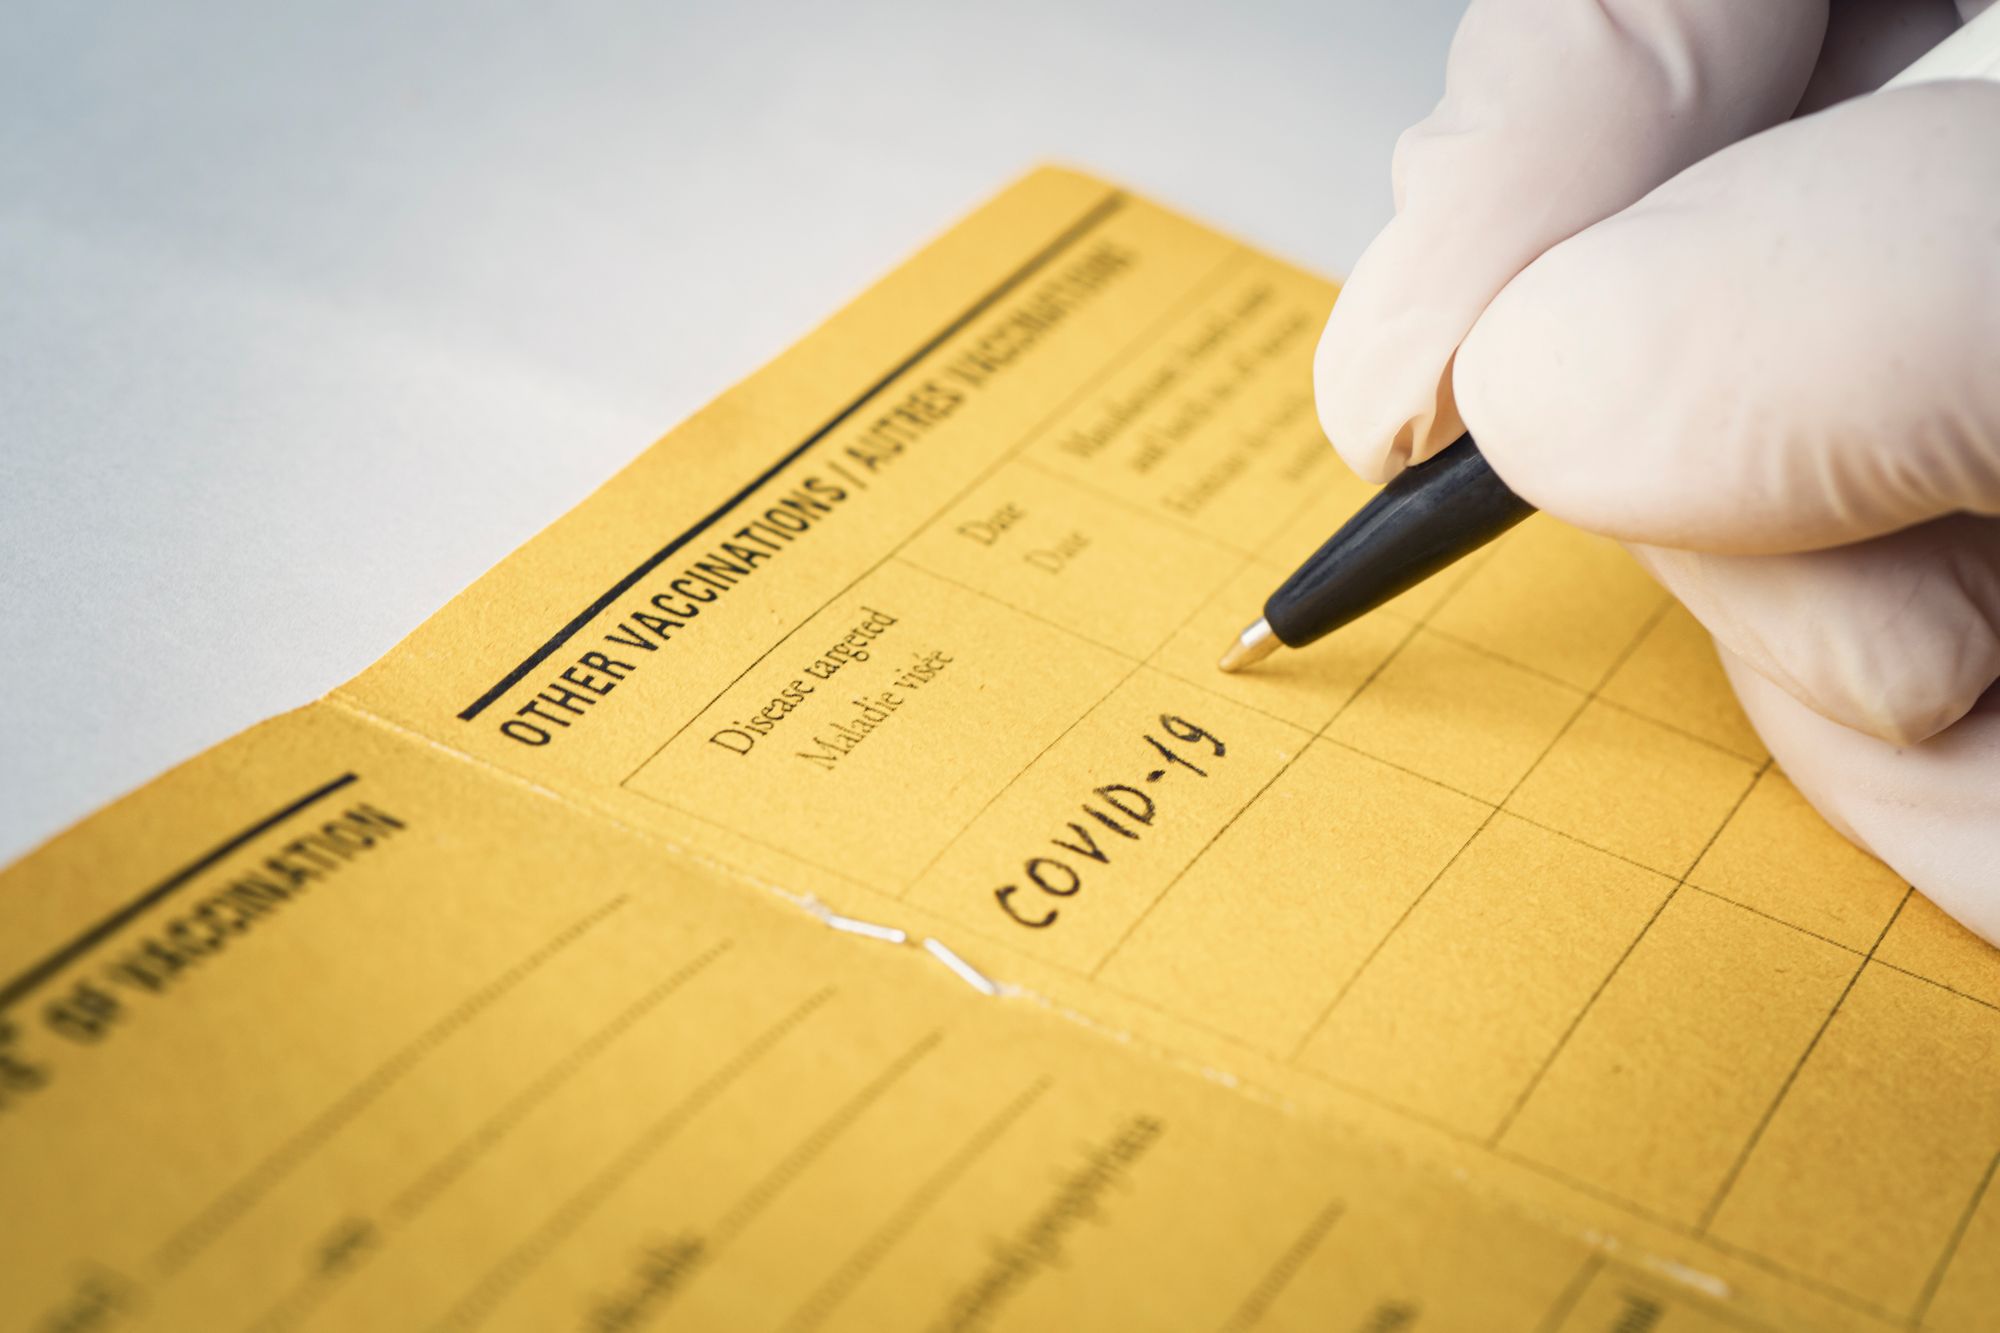

Die südafrikanische Variante des Coronavirus durchbricht den Schutz des Impfstoffs von Biontech in einigen Fällen. Das zeigen vorläufige Daten aus Israel.

Corona-Impfreihenfolge soll noch im Frühjahr abgeschafft werden